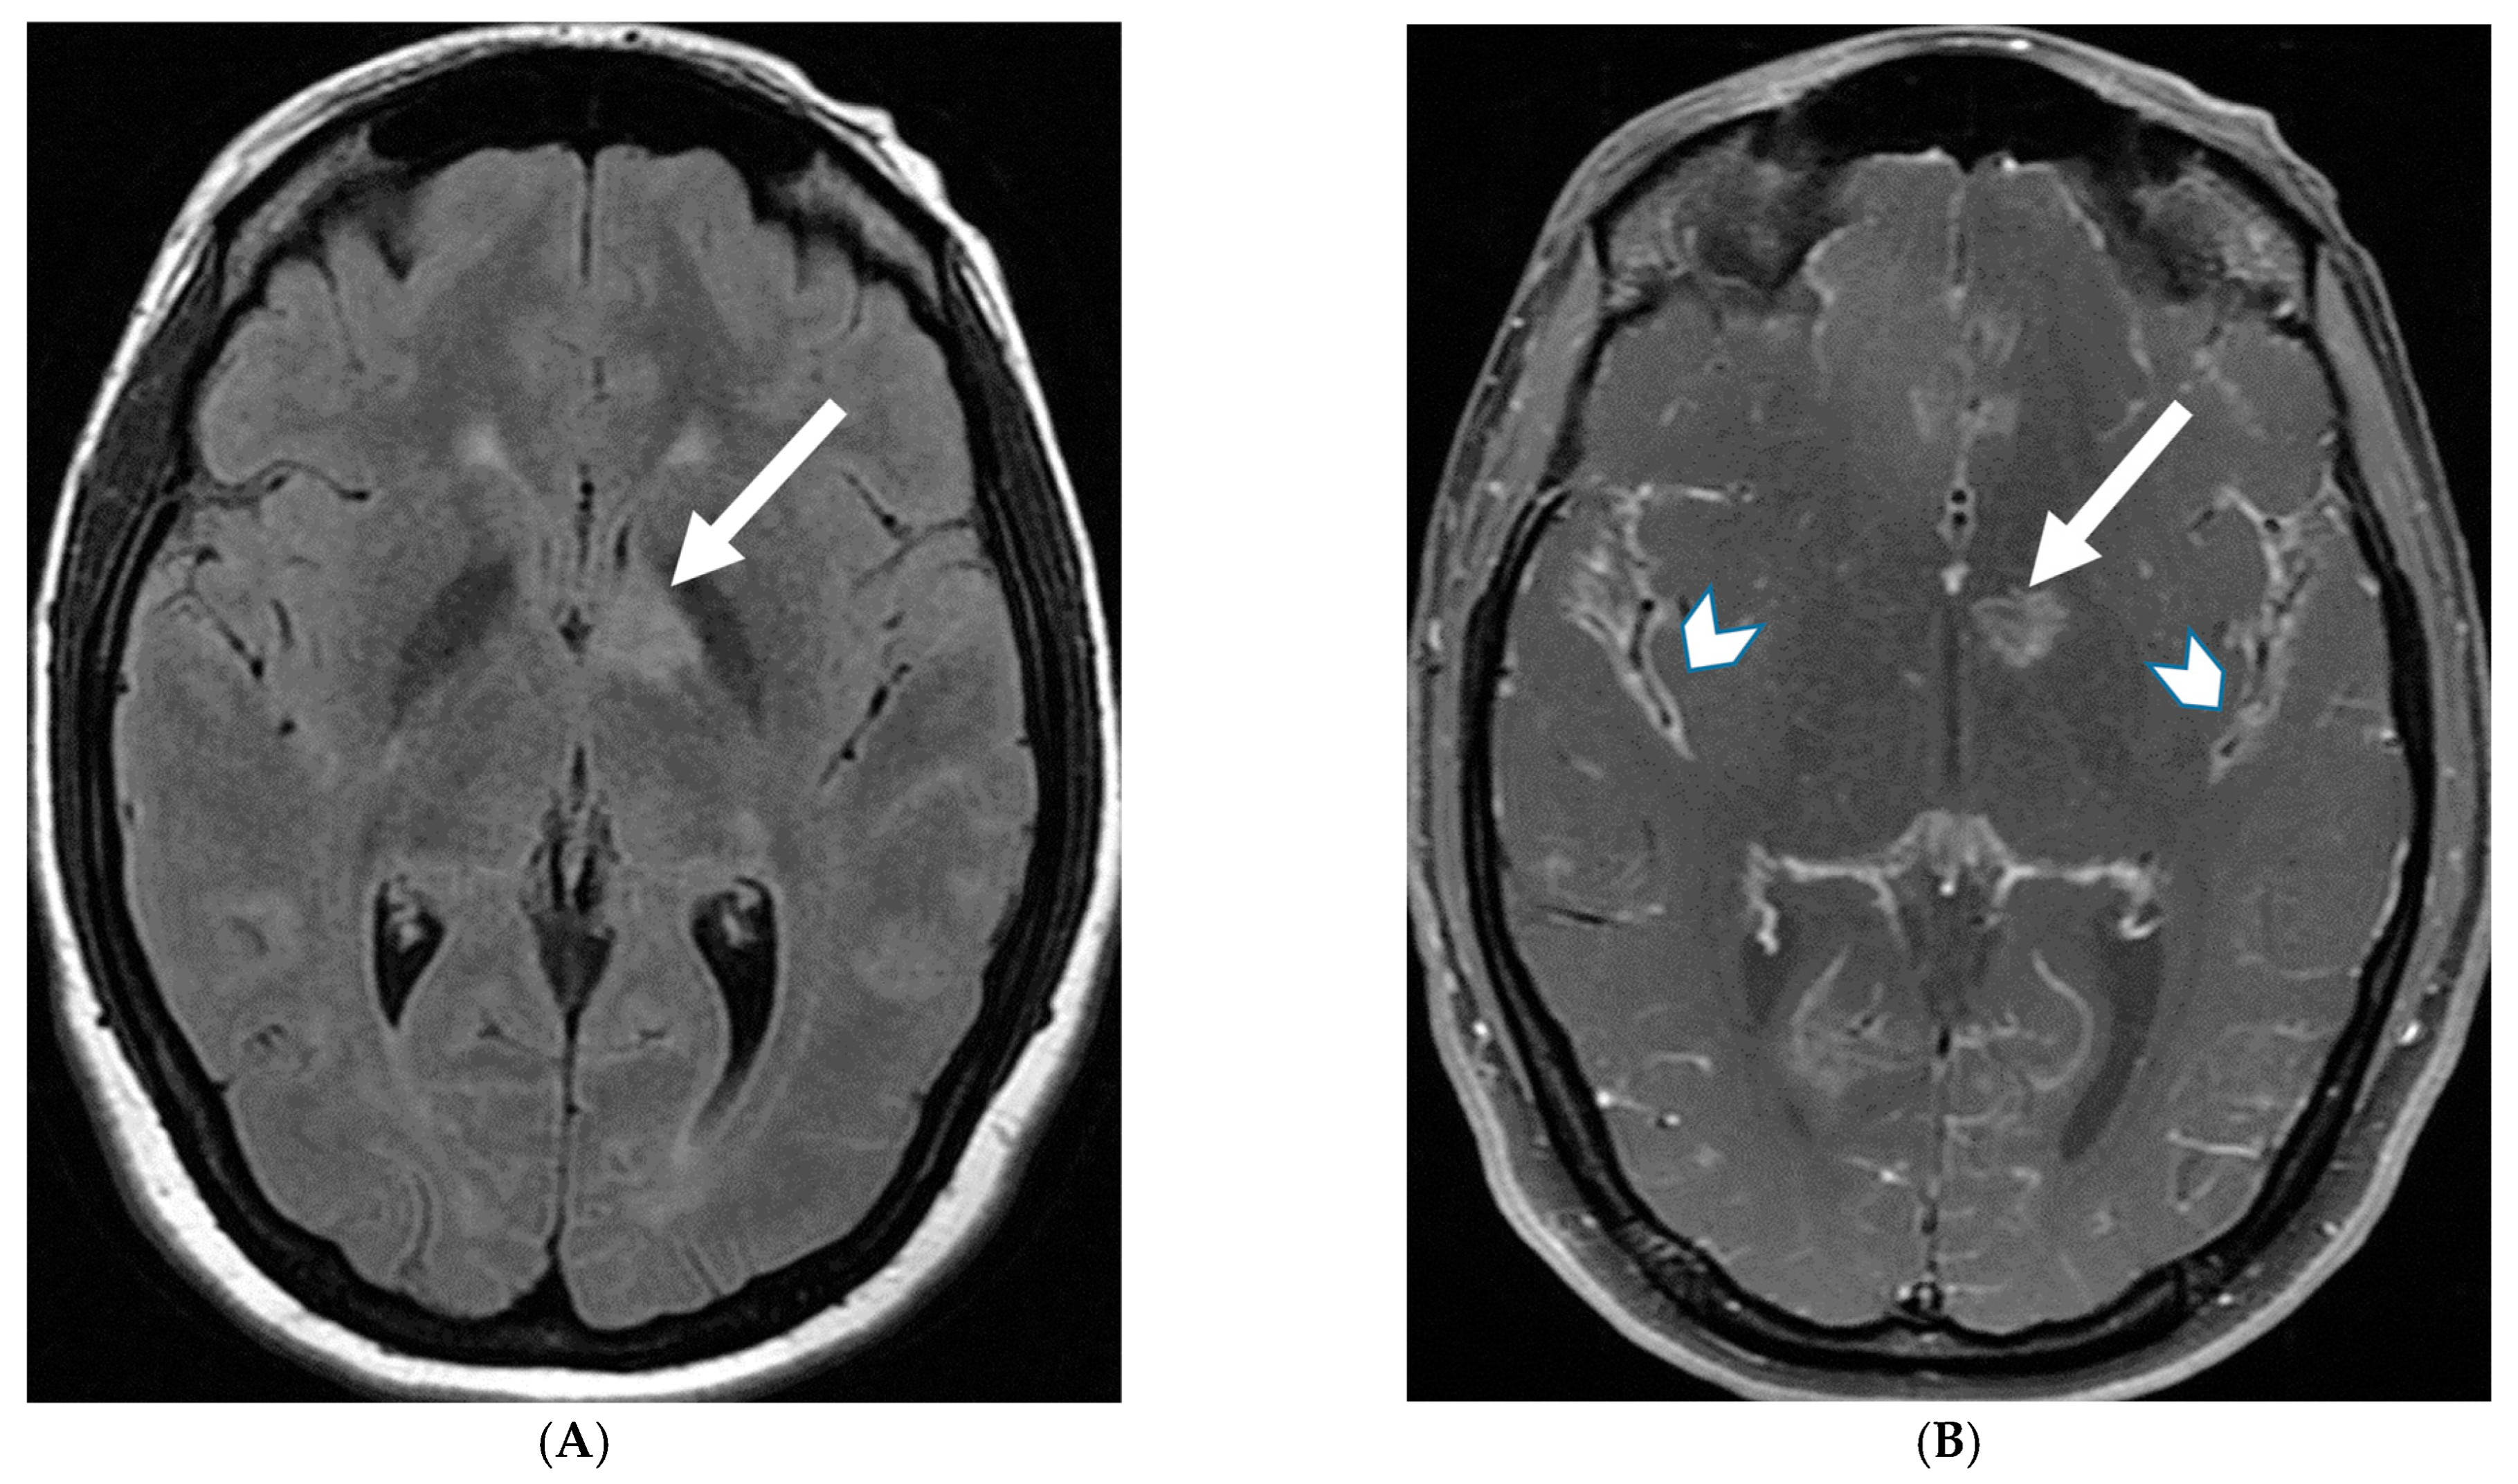

LME has been shown to present early in the disease course and is much more common in children (33%) compared to adults (8%) [107]. Gadde et al. found that 8% of pediatric MOG antibody-associated demyelination cases had only LME without any other central nervous system manifestation. LME when present can be particularly helpful in differentiating from NMOSD [106]. Furthermore, Valencia-Sanchez et al. reported a significant association between LME and cerebral cortical encephalitis in MOG antibody-associated disease. This finding suggests that LME may be an important marker for cortical involvement and potentially more severe disease (Figure 21) [108].

Figure 21.

Sagittal T2 (A,B), axial FLAIR (C), axial T2 cervical spine (D) at the level of C7 vertebral body and Axial T2 orbits (E): 12-year-old girl presented with right focal motor seizure and left temporal lobe slowing on electroencephalogram (EEG). Right eye vision loss and irritability. Ill-defined areas of signal abnormalities are identified within the RIGHT mesial temporal lobe and bilateral medulla (white arrows). FLAIR hyperintensity is identified on the left central sulcus (black arrow). Small focus of signal abnormality is seen on the right side of the cord at the 7th cervical vertebra (C7) (dashed arrow). There is also bilateral papilledema (arrowheads). Post contrast axial T1 (F,G), axial T1 orbits (H) and axial T1 cervical spine at C7 (I): Asymmetric LME (black arrows) predominantly involving the left cerebral hemisphere, with minimal right parietal involvement is seen. Ill-defined enhancement in the right mesial temporal lobe, and right greater than left medulla (white arrows) corresponds to the signal abnormality. There is right greater than left, optic nerve enhancement (curved arrow). Single small enhancing lesion in the spinal cord on the right at the level of C7 corresponds to the signal abnormality (dashed arrow). Features favor a demyelinating process. MOG antibodies were positive at 1:20 in keeping with Myelin oligodendrocyte glycoprotein (MOG) antibody disease (MOGAD).